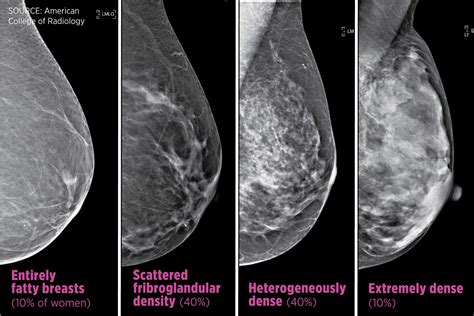

Normal mammogram images can vary depending on the individual's breast tissue density. Breast tissue density is categorized into four types:

Category Description

Almost entirely fatty The breasts are mostly composed of fatty tissue, making it easier to detect abnormalities.

Scattered areas of fibroglandular density The breasts have some dense tissue and some fatty tissue, which can make detection slightly more challenging.

Heterogeneously dense The breasts have a significant amount of dense tissue, which can obscure small abnormalities.

Extremely dense The breasts are almost entirely composed of dense tissue, making it the most difficult to detect abnormalities.